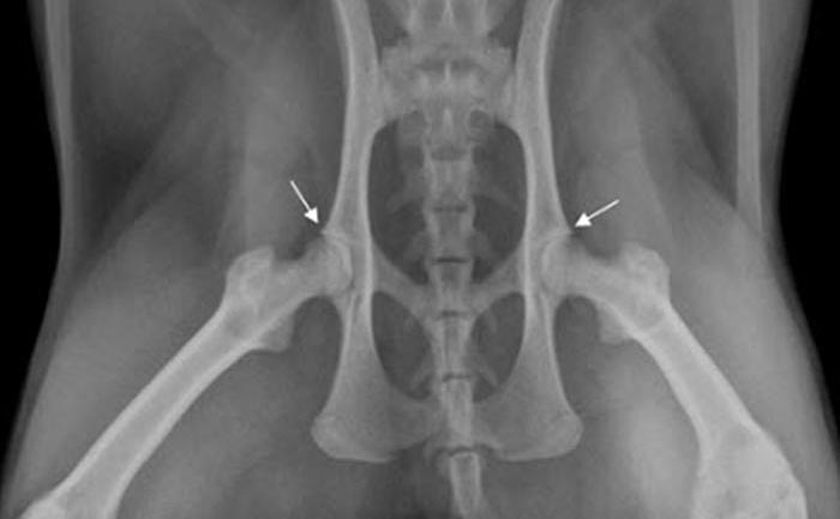

La principale méthode de diagnostic de la dysplasie de la hanche chez les animaux est la radiographie. Cet examen est généralement réalisé sous sédation afin d'assurer un bon alignement articulaire. En cas de dysplasie de la hanche, les radiographies révèlent un défaut d'alignement de la tête fémorale et de l'acétabulum. Au stade dégénératif, on observe une déformation des surfaces osseuses et une croissance anormale (fibrose) des tissus environnants.